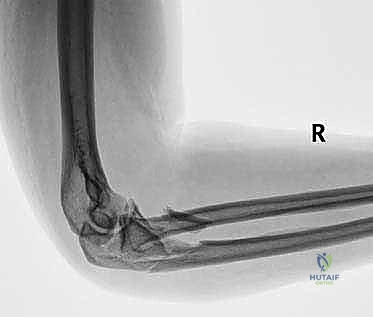

FIG 1 • Plain AP radiograph typically demonstrates fracture pattern.

FIG 1 • Plain lateral radiograph typically demonstrates fracture pattern.

FIG 1 • Plain oblique radiograph typically demonstrates fracture pattern.